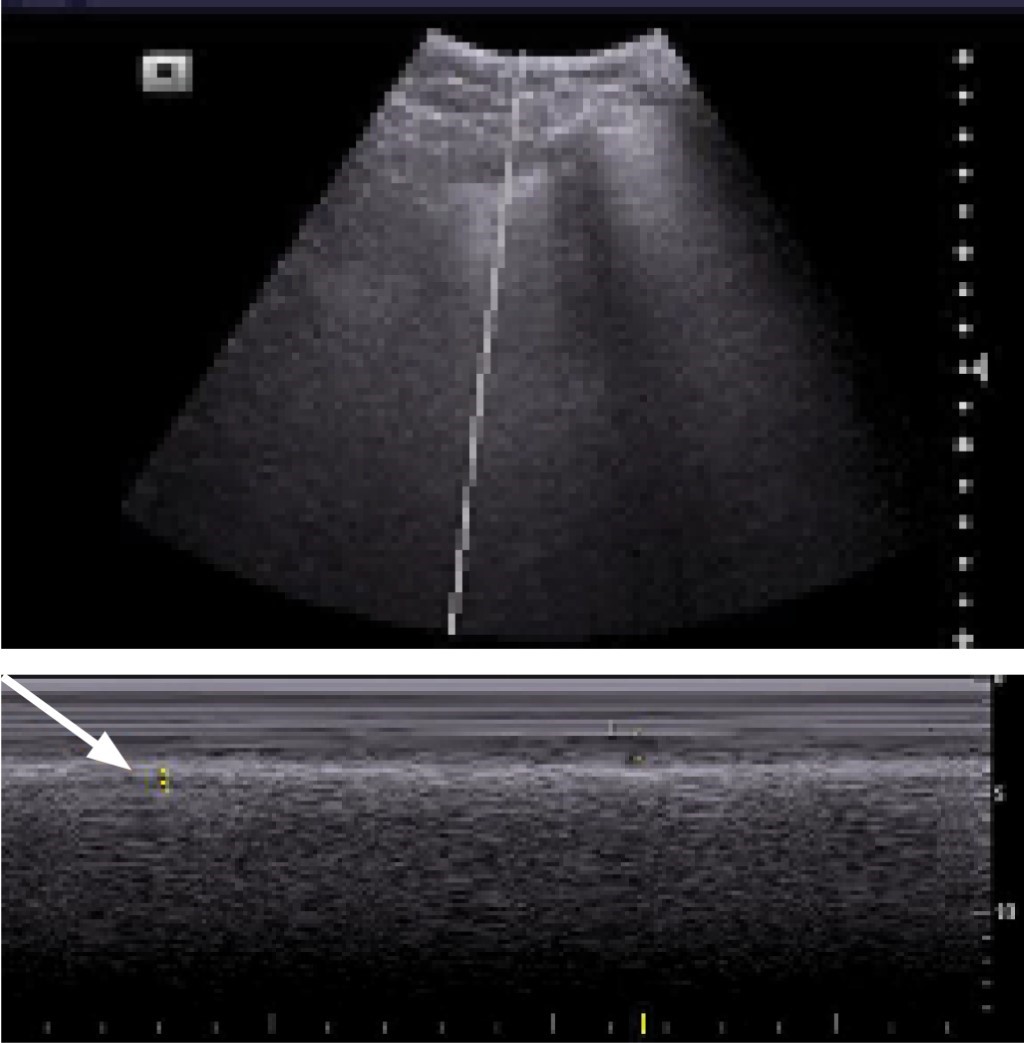

Posterior a la identificación de la consolidación subpleural en modo B (Figuras 1 y 2) se realizará la medida del tamaño de ésta en modo M, colocando el marcador al centro de la consolidación y se procederá a evaluar el movimiento respiratorio cíclico del pulmón y posteriormente se congelará la imagen al observar por lo menos dos movimientos cíclicos y se procederá a la medición al final de la espiración, en sus medidas longitudinal y transversal, colocando el cursor para su medida en mm (Figuras 3 y 4).

Las consolidaciones subpleurales se identificaron como lesiones hipoecoicas localizadas en la región subpleural, para ser más específicos por debajo de la pleura, o bien descritas como "signo de la pleura cortada", las cuales presentan cambios en su tamaño a la inspiración y espiración.

En los pacientes en los que se realizó ultrasonido pulmonar tanto en modo B como en modo M se obtuvieron diferentes imágenes y se logró medir el tamaño de la consolidación, obteniendo una mejor calidad y tamaño en las imágenes en modo M, principalmente en aquellos pacientes en los que se utilizó un transductor convexo. Todos los pacientes en los que se identificaron consolidaciones subpleurales de mayor tamaño cursaban con cuadros graves de la enfermedad, como síndrome de distrés respiratorio severo y aquellos que no se encontraban intubados, pero en los que se identificaron consolidaciones subpleurales, tuvieron mal pronóstico y evolucionaron a deterioro y finalmente requirieron manejo avanzado de la vía aérea.

Debido a que en modo B con el transductor convexo es difícil medir y poder ser más objetivo en la magnitud de estas consolidaciones, propusimos la medición de dichas consolidaciones con un transductor convexo y en modo M.

La técnica que proponemos es medir dichas consolidaciones principalmente en modo M, ya que en modo B no se pueden identificar claramente los bordes de la consolidación, lo cual dificulta la medición durante la inspiración y espiración, siendo este último el valor que se tomará en cuenta, como se observa en las imágenes.

Figura 3

Figura 4